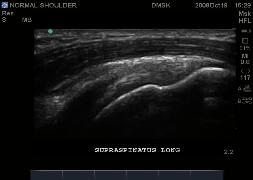

Normal Shoulder Images